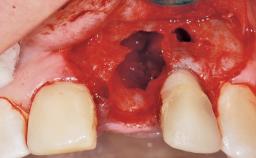

Late Placement of an Implant in a Maxillary Left Central Incisor Site

A 30-year-old female patient had lost tooth 21 and was referred to our clinic for consultation and treatment. Due to advanced apical infection, tooth 21 had been extracted two months earlier at another clinic and an acrylic-resin tooth had been bonded to the adjacent teeth. The patient desired implant treatment to avoid any damage to the adjacent natural teeth. While the patient had no history of any systemic disorder, she was a heavy smoker and exhibited medium to advanced periodontitis in the entire jaw. After the initial treatment to achieve a pocket probing depth of less than 4 mm and no bleeding on probing, a decrease in the height of the papillae mesial and distal to the extraction site and overall gingival recession were observed.

Bone Augmentation Horizontal|Staged

Augmentation Materials Autogenous chips|Membrane